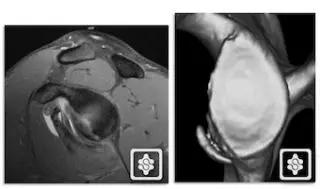

1. Hill-Sachs 损伤和反 Hill-Sachs 损伤

肩关节脱位时,肱骨头和关节盂发生撞击,肱骨头表面凹陷性骨折。

肩关节前脱位时发生的肱骨头后外侧凹陷性骨折,是经典的 Hill-Sachs 损伤(Hill-Sachs lesion);

而肩关节后脱位时发生的肱骨头前内侧凹陷性骨折,是反 Hill-Sachs 损伤(Reverse Hill-Sachs lesion/ McLaughlin lesion)。

Hill-Sachs 损伤的 MR 片(来源:Hill-Sachs Injuries of the Shoulder)

MRI 示反 Hill-Sachs 损伤程度 (来源:Anatomical Reconstruction of Reverse Hill-Sachs Lesions Using the Underpinning Technique. Orthopedics May 2012 - Volume 35 · Issue 5: e752-e757)